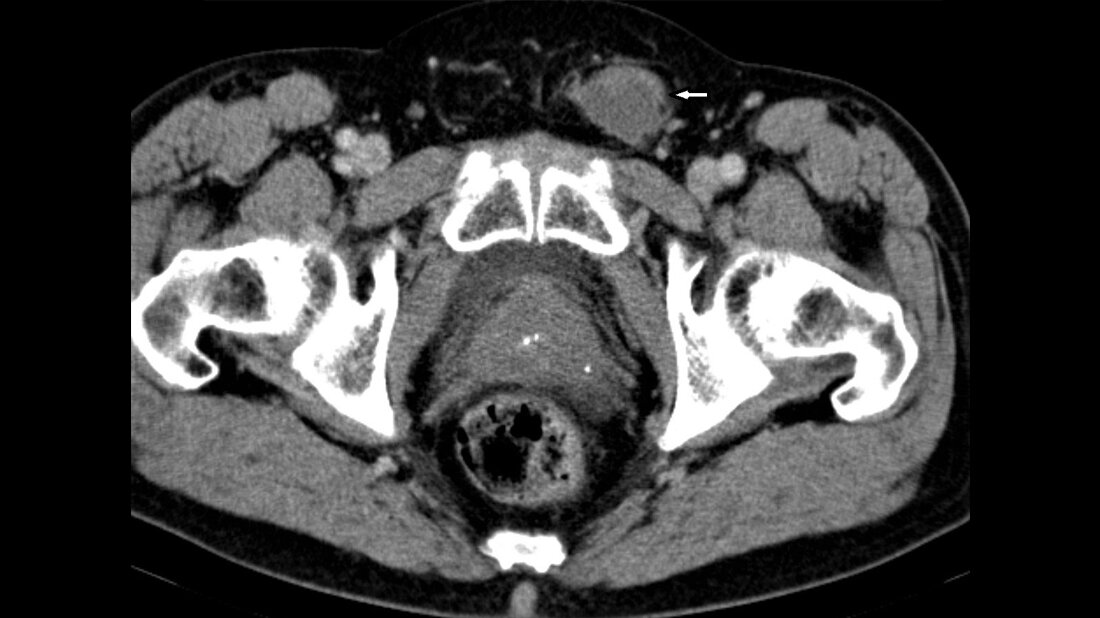

Anomalien und Normvarianten – Interne Veränderungen 2.18: Maldescensus testis

Der Maldescensus testis ist die häufigste genitale Malformation der Jungen und hat ein erhöhtes Risiko der Infertilität und malignen Entartung. Die Therapie mit humanem Choriongonadotropin ist oft erfolgreich, sonst die operative Behandlung mit Orchiopexie.

Schlüsselwörter: Maldescensus testis, Röntgen, Sonografie, CT, MRT